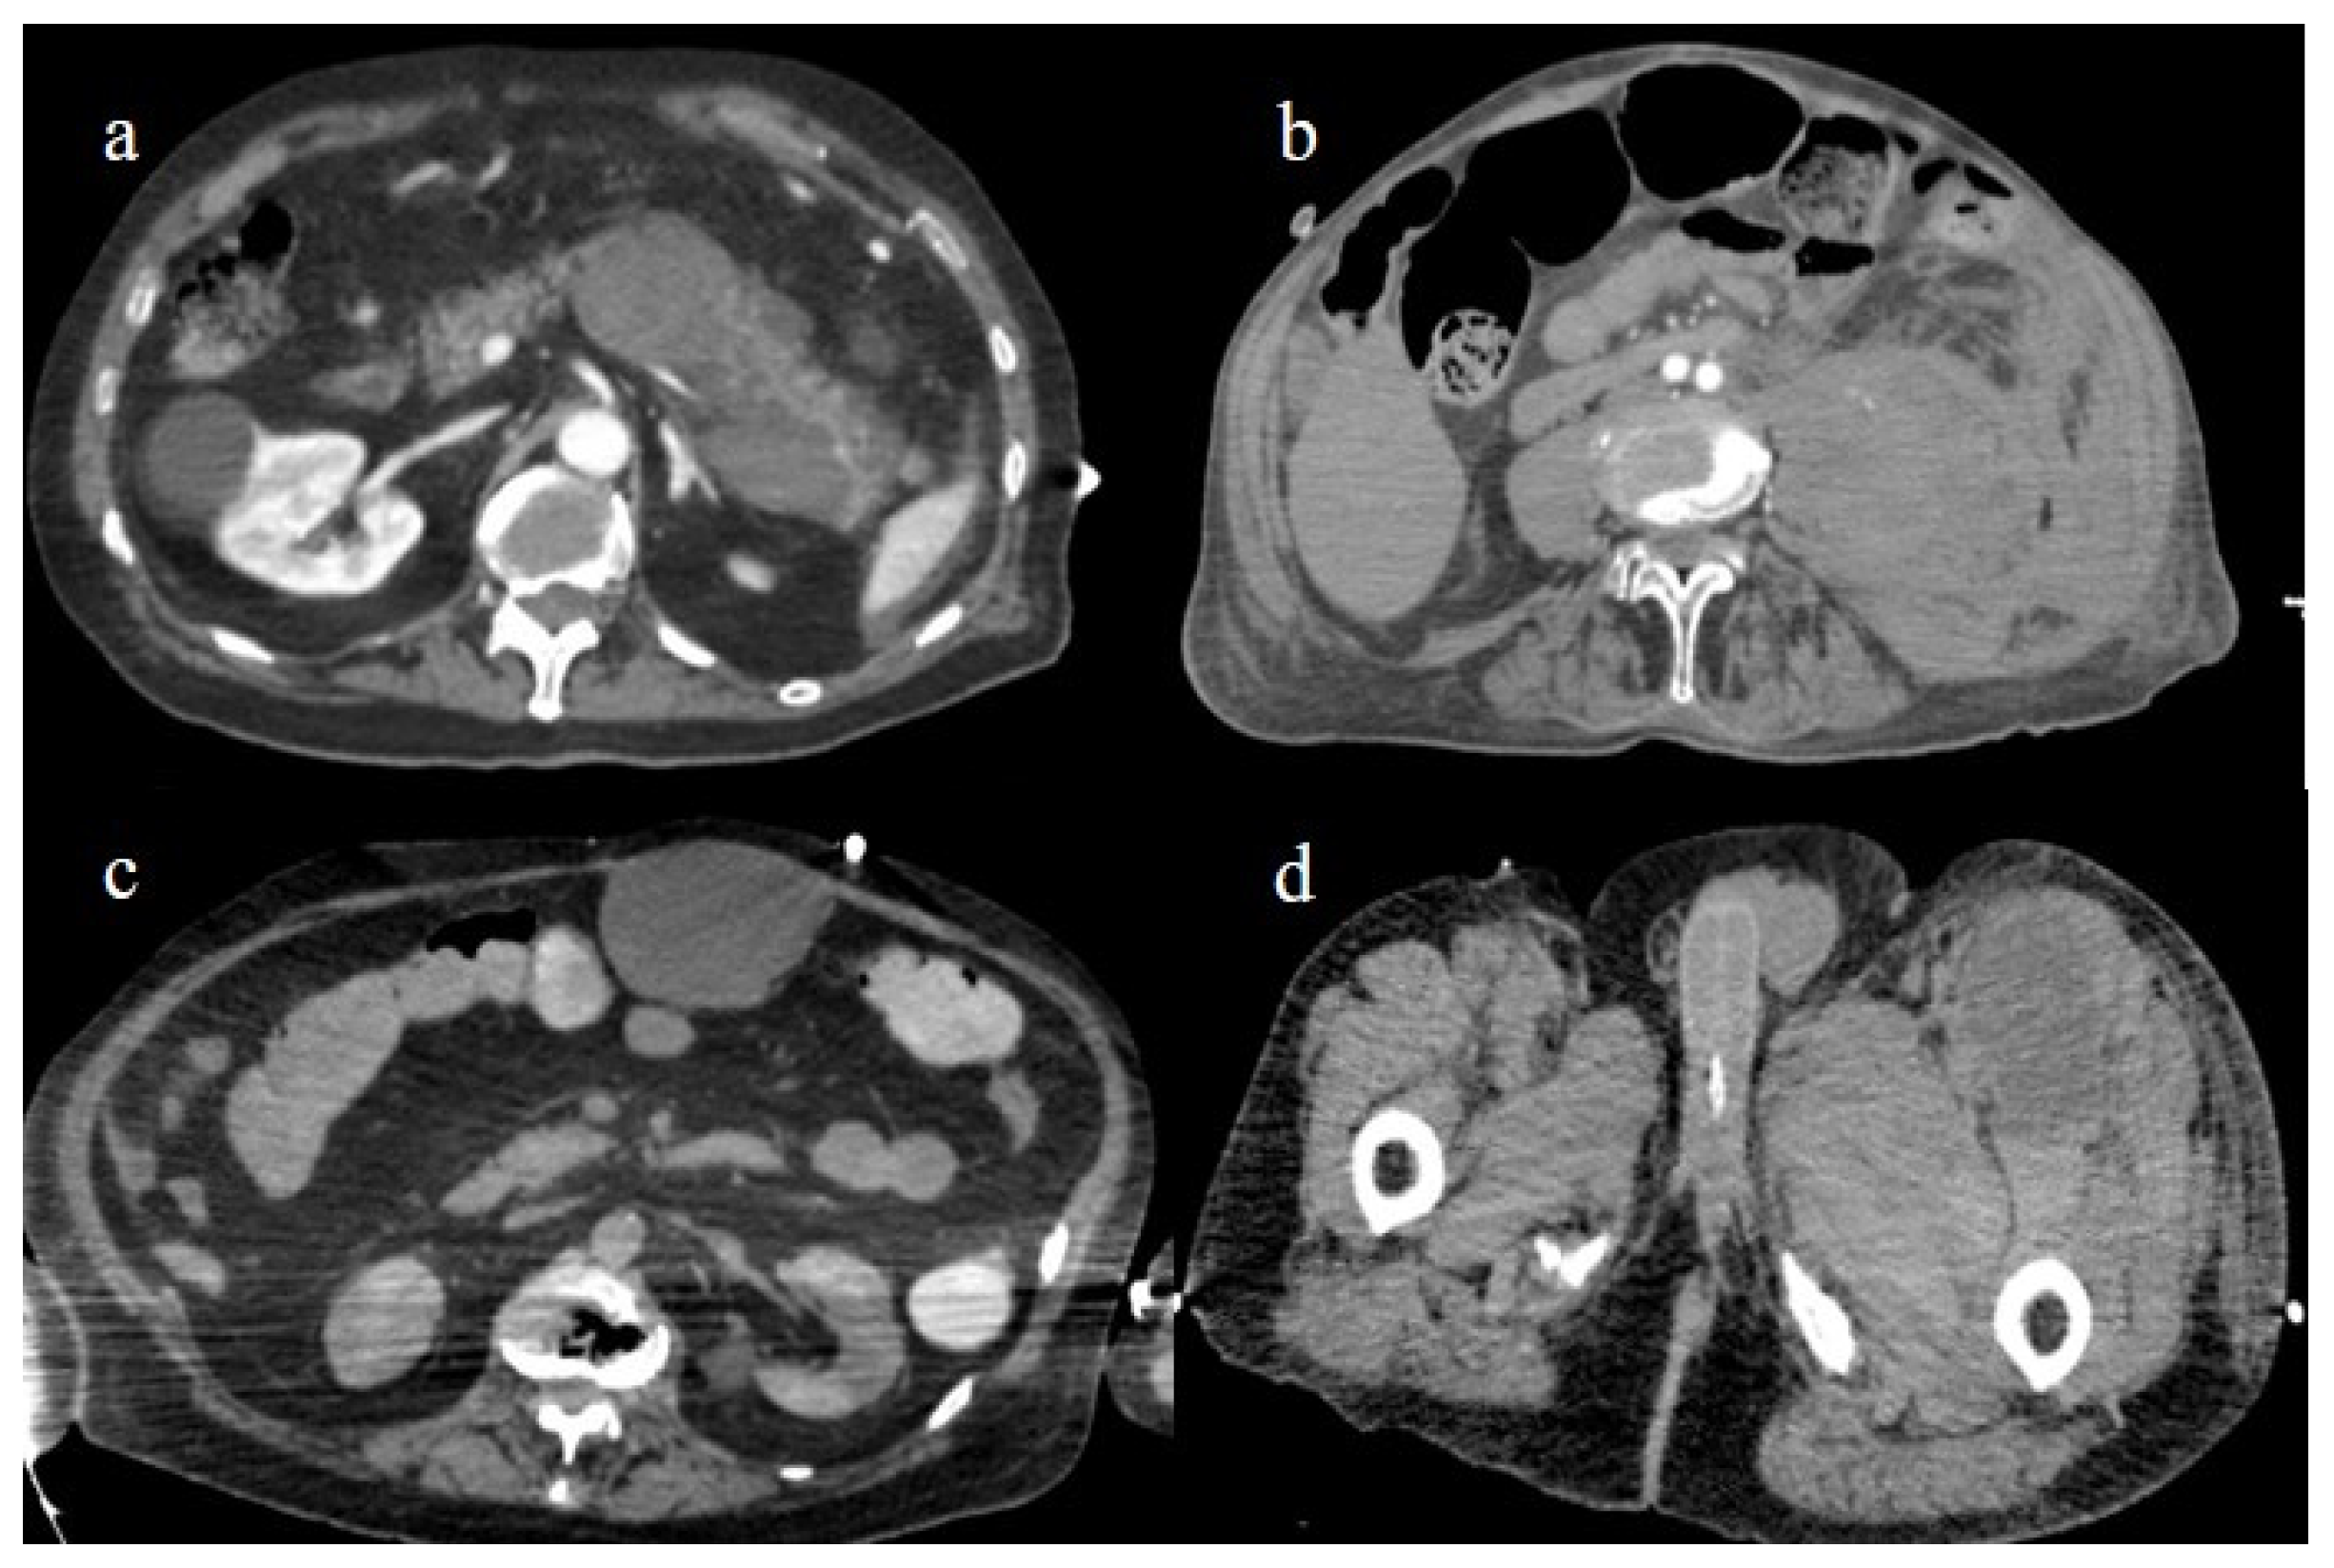

4.2. Splenic and Renal Infarction

4.3. Hemorrhagic Abdominal Complications

- Bonaffini, P.A.; Franco, P.N.; Bonanomi, A.; Giaccherini, C.; Valle, C.; Marra, P.; Norsa, L.; Marchetti, M.; Falanga, A.; Sironi, S. Ischemic and hemorrhagic abdominal complications in COVID-19 patients: Experience from the first Italian wave. Eur. J. Med. Res. 2022, 27, 1–9. [Google Scholar] [CrossRef]

- Evrev, D.; Sekulovski, M.; Gulinac, M.; Dobrev, H.; Velikova, T.; Hadjidekov, G. Retroperitoneal and abdominal bleeding in anticoagulated COVID-19 hospitalized patients: Case series and brief literature abdominal bleeding in anticoagulated COVID-19 hospitalized patients: Case series and brief literature review. World J. Clin. Cases 2023, 11, 1528–1548. [Google Scholar] [CrossRef] [PubMed]

- Sposato, B.; Croci, L.; Di Tomassi, M.; Puttini, C.; Olivieri, C.; Alessandri, M.; Ronchi, M.C.; Donati, E.; Garcea, A.; Brazzi, A.; et al. Spontaneous abdominal bleeding associated with SARS-CoV-2 infection: Causality or coincidence? Acta Biomed. 2021, 92, e2021199. [Google Scholar] [PubMed]

- Mahmoudabadi, H.Z.; Hadadi, A.; Fattahi, M.R.; Kafan, S.; Ashouri, M.; Allahbeigi, R.; Hajebi, R. Rectus Sheath Hematoma in COVID-19 Patients as a Mortal Complication: A Retrospective Report. Int. J. Clin. Pract. 2022, 2022, 7436827. [Google Scholar] [CrossRef]

- Castro, G.R.A.; Collaço, I.A.; Bosco, C.L.B.D.; Corrêa, G.G.; Bosco, G.B.D.; Corrêa, G.L. Splenic infarction as a complication of covid-19 in a patient without respiratory symptoms: A case report and literature review. IDCases 2021, 24, e01062. [Google Scholar] [CrossRef] [PubMed]

- Prentice, G.; Wilson, S.; Coupland, A.; Bicknell, S. Complete splenic infarction in association with COVID-19. BMJ Case Rep. 2021, 14, e246274. [Google Scholar] [CrossRef] [PubMed]

- Al Suwaidi, S.; Alakasheh, B.J.; Al-Ozaibi, L.S. Splenic Infarction in a COVID-19 Patient without Respiratory Symptoms. Dubai Med. J. 2022, 5, 74–77. [Google Scholar] [CrossRef]

- Childers, J.; Do, T.V.C.; Smith, F.; Vangara, A.; Ganti, S.S.; Akella, R. Incidental and Asymptomatic Splenic Infarction and Infrarenal Thrombus in a COVID-19 Patient. Cureus 2022, 14, e26555. [Google Scholar] [CrossRef] [PubMed]

- Post, A.; den Deurwaarder, E.S.G.; Bakker, S.J.L.; de Haas, R.J.; van Meurs, M.; Gansevoort, R.T.; Berger, S.P. Kidney Infarction in Patients with COVID-19. Am. J. Kidney Dis. 2020, 76, 431–435. [Google Scholar] [CrossRef]

- Jana, K.; Janga, K.C.; Greenberg, S.; Kumar, K. Bilateral renal infarction with COVID-19 pneumonia: A case report. Oxf. Med. Case Rep. 2021, 2021, omab121. [Google Scholar] [CrossRef]

- Al-Mashdali, A.F.; Alwarqi, A.F.; Elawad, S.M. Simultaneous renal infarction and splenic infarction as a possible initial manifestation of COVID-19: A case report. Clin. Case Rep. 2021, 9, 4819. [Google Scholar] [CrossRef]

- Brem, F.L.; Abu Al Tayef, T.; Rasras, H.; El Mahi, O.; El Ouafi, N.; Zakaria, B. Concomitant renal and splenic infarctions in a COVID-19-patient with a catastrophic thrombotic syndrome. Radiol. Case Rep. 2022, 17, 4030–4033. [Google Scholar] [CrossRef]

- Ramanathan, M.; Chueng, T.; Fernandez, E.; Gonzales-Zamora, J. Concomitant renal and splenic infarction as a complication of COVID-19: A case report and literature review. Infez. Med. 2020, 28, 611–615. [Google Scholar]

- Mavraganis, G.; Ioannou, S.; Kallianos, A.; Rentziou, G.; Trakada, G. A COVID-19 Patient with Simultaneous Renal Infarct, Splenic Infarct and Aortic Thrombosis during the Severe Disease. Healthcare 2022, 10, 150. [Google Scholar] [CrossRef]

- Mahboubi-Fooladi, Z.; Arabi, K.P.; Khazaei, M.; Nekooghadam, S.; Shadbakht, B.; Moharamzad, Y.; Taheri, M.S. Parenteral Anticoagulation and Retroperitoneal Hemorrhage in COVID-19: Case Report of Five Patients. SN ComPract. Clin. Med. 2021, 3, 2005–2010. [Google Scholar] [CrossRef] [PubMed]

- Dubovský, M.; Hajská, M.; Panyko, A.; Vician, M. Severe Retroperitoneal Hemorrhage in a COVID-19 Patient on a Therapeutic Dose of Low Molecular Weight Heparin: A Case Report. Cureus 2022, 14, 26275. [Google Scholar] [CrossRef] [PubMed]

- Yeoh, W.C.; Lee, K.T.; Zainul, N.H.; Alwi, S.B.S.; Low, L.L. Spontaneous retroperitoneal hematoma: A rare bleeding occurrence in COVID-19. Oxf. Med. Case Rep. 2021, 2021, omab081. [Google Scholar] [CrossRef] [PubMed]

- Shah, M.; Colombo, J.P.; Chandna, S.; Rana, H. Life-Threatening Retroperitoneal Hematoma in a Patient with COVID-19. Case Rep. Hematol. 2021, 2021, e8774010. [Google Scholar] [CrossRef]

- Belfiore, M.P.; Russo, G.M.; Gallo, L.; Atripaldi, U.; Tamburrini, S.; Caliendo, V.; Impieri, L.; Del Canto, M.T.; Ciani, G.; Parrella, P.; et al. Secondary Complications in COVID-19 Patients: A Case Series. Tomography 2022, 8, 1836–1850. [Google Scholar] [CrossRef]